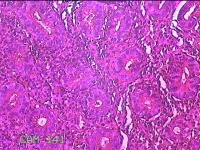

胃窦粘膜

性别

女

年龄

52岁

临床诊断

胃食管反流?;慢性胃炎

一般病史

吞咽困难2年余。

标本名称

大体所见

灰白粉红色组织小米大一团。

图3

有可能是慢性炎,片子这个效果,猜起来比较困难,